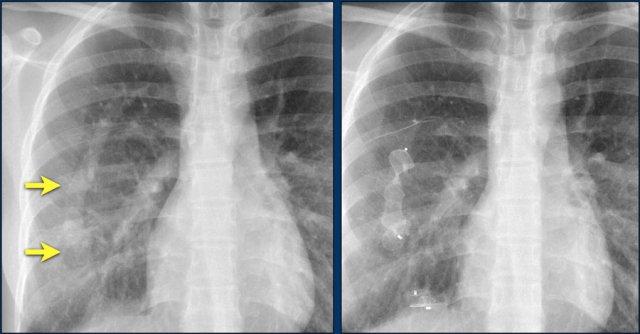

Hình ảnh bên trái cho thấy bệnh nhân có ICD được đặt đúng vị trí.

Vài tháng sau, thiết bị hoạt động không bình thường do hộp ICD và điện cực bị xoay (mũi tên vàng) và co rút lại (mũi tên trắng).

Đây là một bệnh nhân khác mắc hội chứng Twiddler.

Lưu ý hình ảnh điện cực bị cuộn xoắn gần máy tạo nhịp và tại đầu điện cực trong thất phải (mũi tên).